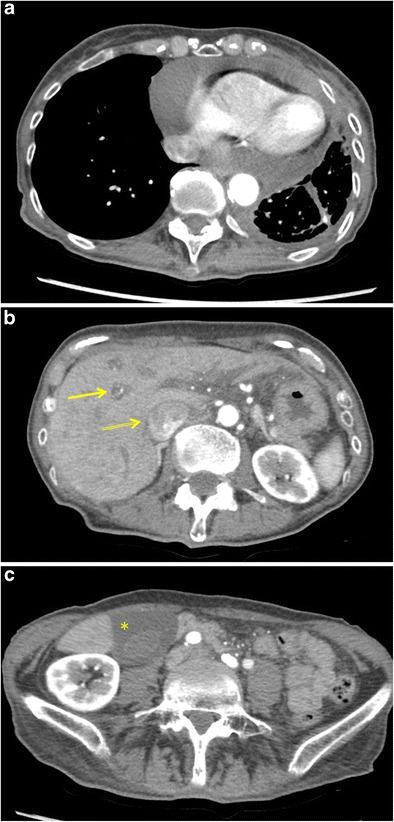

Lung cancer patients often experience potentially life-threatening medical urgencies and emergencies, which may be a direct or indirect result of the underlying malignancy. This pictorial review addresses the most common thoracic, neurological and musculoskeletal medical emergencies in lung cancer patients, including superior vena cava syndrome, pulmonary embolism, spontaneous pneumothorax, cardiac tamponade, massive haemoptysis, central airway obstruction, oesophagorespiratory fistula, malignant spinal cord compression, carcinomatous meningitis, cerebral herniation and pathological fracture. Emphasis is placed on imaging findings, the role of different imaging techniques and a brief discussion of epidemiology, pathophysiology and therapeutic options. Since early diagnosis is important for adequate patient management and prognosis, radiologists have a crucial role in recognising and communicating these urgencies and emergencies.

肺癌患者常经历可能危及生命的医学急症,这可能是潜在恶性肿瘤的直接或间接结果。本图像综述探讨了肺癌患者最常见的胸部、神经和肌肉骨骼医学急症,包括上腔静脉综合征、肺栓塞、自发性气胸、心脏压塞、大量咯血、中央气道阻塞、食管气管瘘、恶性脊髓压迫、癌性脑膜炎、脑疝和病理性骨折。重点介绍影像学表现、不同成像技术的作用,并简要讨论流行病学、病理生理学和治疗选择。由于早期诊断对患者的充分管理和预后很重要,放射科医生在识别和传达这些急症方面起着关键作用。